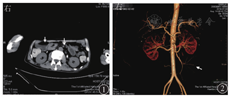

患者男,56岁,因"反复腹胀伴恶心、呕吐6个月"于2018年6月18日入住哈尔滨医科大学附属第一医院。患者6个月前无明显诱因出现腹部胀痛,以脐周为主,无放射痛,伴恶心、呕吐,呕吐物为黄绿色水样物,同时肛门排气减少。对症治疗后症状好转。2018年5月患者再次出现上述症状,发作时排气减少,呕吐胃内容物后症状可缓解。自行购买益生菌、中药服用半个月后自觉好转。2018年6月11日患者出现相同症状,恶心、呕吐较前加重,呕吐物为食物伴有胆汁。6月14日于当地医院行胃肠镜检查,诊断为胆汁反流性胃炎,给予相应治疗后未见好转,腹胀加重,排气、排便消失。6月18日急诊入住哈尔滨医科大学附属第一医院,考虑肠梗阻,入院时体格检查示无欲貌,意识不清,慢性病容,血压为98/62 mmHg(1 mmHg=0.133 kPa),心率为100次/min,腹部饱满,腹部叩诊呈鼓音。给予胃肠减压、禁食水、补液、营养支持治疗。6月23日患者视物重影,目光呆滞;25日出现嗜睡症状,病情进行性加重;27日因晕厥转入重症监护病房,给予气管插管、抗炎、对症支持治疗。2018年7月5日行头颅MRI检查,确诊韦尼克(Wernicke)脑病;7月9日行腹部CT检查见右侧肠管扩张、积气、积液,左中下腹局部肠系膜旋转(图1)。腹部计算机断层扫描血管造影(computed tomography angiography, CTA)检查见肠系膜上动脉及其分支移位、旋转(图2)。神经内科和普外科会诊后建议经口置入肠梗阻导管,经肠梗阻导管注入少量流食,口服肠道益生菌,辅以胃肠黏膜保护剂,补充维生素B1、B6,纠正电解质紊乱,以及充分静脉营养支持等治疗。2018年8月10日患者腹胀减轻,无恶心、呕吐,有自主排气、排便,意识好转,给予经口半流质饮食;半流质饮食6 d后患者腹胀加重,伴恶心、呕吐,呕吐物为胆汁,排气、排便消失。回顾病史,患者住院期间反复多次出现禁食数日后症状减轻,半流质饮食数日后症状加重。2018年8月16日行直立位上消化道造影检查示近段空肠扩张,呈螺旋状,可见液气平面,动态观察可见肠管逆蠕动(图3)。小肠镜检查可见距幽门40 cm处小肠走行扭曲,呈"S"形,其口端肠腔明显扩张、绒毛结构变平、环形皱襞消失(图4)。患者于2018年9月24日行腹腔镜下小肠切除吻合术治疗,术中见近段小肠和肠系膜血管顺时针旋转(图5),远端梗阻扩张空肠位于肠管穿入肠系膜处,由对侧小肠系膜穿出,延续至回盲部,术中诊断为中肠旋转不良。2018年11月20日患者恢复良好而出院。

影像学检查对中肠旋转不良的诊断至关重要。多普勒超声检查对诊断中肠旋转不良具有一定价值,扩张的肠管和肠系膜上静脉以顺时针方向缠绕肠系膜上动脉,扭曲的肠系膜血管构成了漩涡符号,这是典型的旋转不良,甚至肠系膜上静脉反转至肠系膜上动脉的左侧,多普勒超声检查可以清晰地显示该现象[1,5]。腹部CTA成像同样可以清楚地显示肠系膜血管旋转情况,如本病例所示。腹部CT检查显示的漩涡征即螺旋状的肠系膜血管,这种体征并不是特异性的,也可能会在脾脏扭转等其他病理情况下出现。但腹部CT检查可以显示空肠扩张、积气、积液,提示梗阻和显示梗阻部位。据报道,上消化道造影检查判断中肠扭转的准确度为100%[6]。X线动态观察造影剂的通过情况可发现空肠蠕动异常,进而判断空肠梗阻的位置。本病例中,造影剂到达扩张的空肠时明显被稀释,说明空肠梗阻上方有积液,同时该位置的肠管出现逆蠕动现象,这样可以基本明确空肠异常旋转的存在和梗阻的位置。小肠镜检查的优势是可以在直视下进一步判断梗阻是器质性病变还是异常旋转,为手术提供直接证据,本病例经口小肠镜检查可见近段空肠走行扭曲。因此,上消化道造影和小肠镜检查在中肠旋转不良的诊断中具有非常重要的价值。